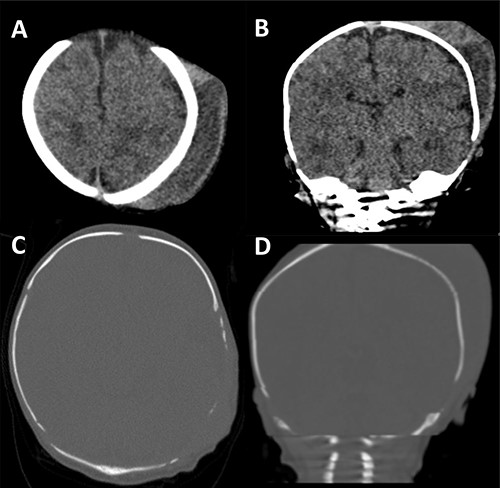

On assessment in the Emergency Department a septic screen revealed a raised C-reactive protein (CRP) of 291 and normal urine dip, chest X-ray and lumbar puncture. He was admitted and started on Benzylpenicillin and Gentamicin. A computed tomography (CT) was performed demonstrating a large collection over the left parietal bone with a moth-eaten appearance of the underlying skull suspicious of osteomyelitis (Fig. 2).

CT scan of our patient. In (A) and (B) the size of the cephalhaematoma can clearly be seen. In (C) and (D) the thinned, moth-eaten appearance of the left parietal region is well demonstrated.